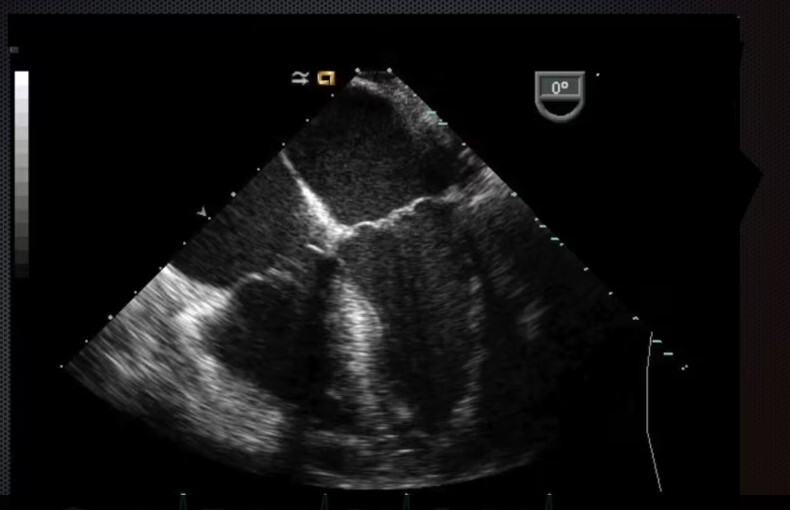

Mid-Esophageal Long Axis View. Multiplane to between 120-140 degrees. Center LVOT. Structures: L atrium, L ventricle, LVOT, aortic valve, R ventricle, posterior & anterior leaflets of mitral valve.